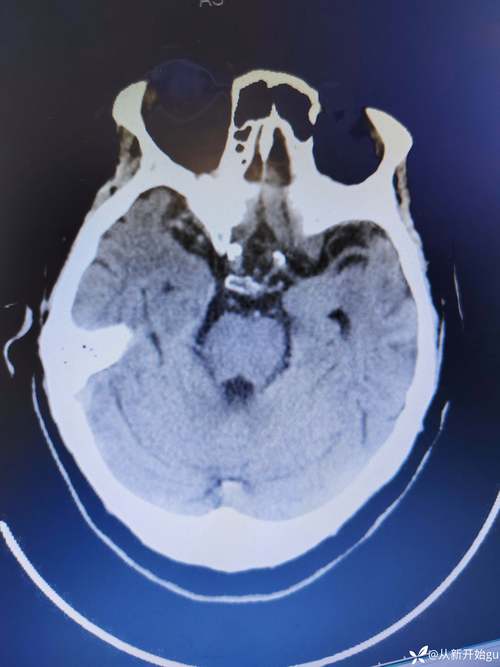

(图片来源网络,侵删)

- 静脉溶栓时间窗: 发病后 5小时内,这是通过注射药物溶解血栓的关键时期,越早越好。

- 动脉取栓时间窗: 发病后 6-24小时内(需经过严格影像学评估),对于大血管堵塞的患者,可以通过介入手术直接取出血栓,恢复血流。

患者被送到医院后,医生会争分夺秒地进行头颅CT等检查,以判断是否符合溶栓或取栓条件。